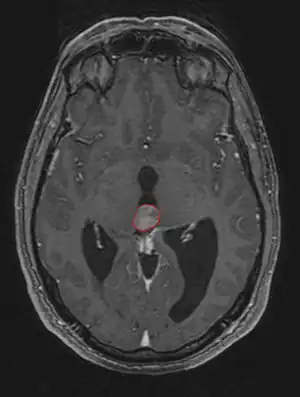

Frequently, paralysis of upward gaze along with several ocular findings such as convergence retraction nystagmus and eyelid retraction also known as Collier's sign and Light Near Dissociation (pupil accommodates but doesn't react to light) are known collectively as Parinaud's syndrome[1] or Dorsal Mid-brain syndrome, are the only physical symptoms seen. This is caused by the compression of the vertical gaze center in the midbrain tectum at the level of the superior colliculus and cranial nerve III. Work-up usually includes Neuro-imaging as seen on the right.